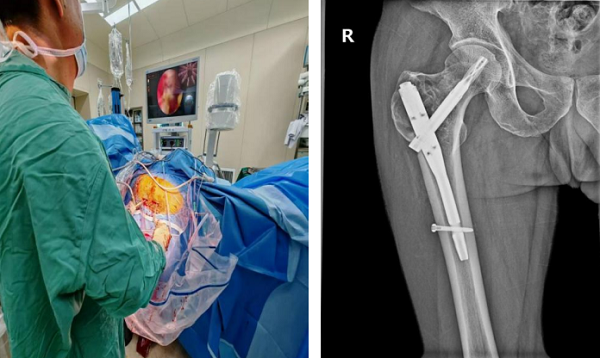

近日,玉溪市人民医院骨外二科专家团队迎来技术突破——成功完成全市首例关节镜辅助下股骨近端骨巨细胞瘤切除术,并同步实施自体髂骨+人工骨植骨术、股骨近端内固定术。该手术不仅为54岁患者杜先生驱散病痛,更填补了玉溪地区关节镜技术应用于良性骨肿瘤治疗的空白,为同类复杂病例提供了新的治疗范式。

手术在全麻下开展,团队创新性采用关节镜辅助技术——通过关节镜的360°无死角视野,精准定位肿瘤病灶,借助专用器械彻底清除肿瘤组织;针对肿瘤较大导致的骨缺损,术中植入自体髂骨与人工骨混合骨材,并进行股骨近端内固定以恢复骨骼稳定性。

与传统手术相比,此次手术全程在关节镜监视下操作,不仅创伤更小,清晰观察瘤腔情况,还能通过低温等离子技术对残留肿瘤细胞进行灭活,有效降低复发风险,同时最大程度保护周围健康组织。

术后恢复效果超出预期:杜先生在术后第二天即可下床拄拐进行患肢不负重行走训练;术后1个月复查时,其髋部疼痛完全缓解,已能实现完全负重行走,影像学检查显示肿瘤病灶无扩大迹象,骨骼愈合情况良好。

据了解,关节镜辅助技术应用于良性骨肿瘤切除,是当前关节镜领域的创新方向,目前省内尚无相关临床应用报道。此次玉溪市人民医院完成的首例手术,不仅验证了该技术在治疗内生性良性骨肿瘤中的显著优势(创伤小、恢复快、复发率低),更标志着玉溪在骨肿瘤微创治疗领域迈出了关键一步。未来,骨外二科将继续探索微创技术在骨科疾病中的应用,为患者提供更优质、更精准的医疗服务。